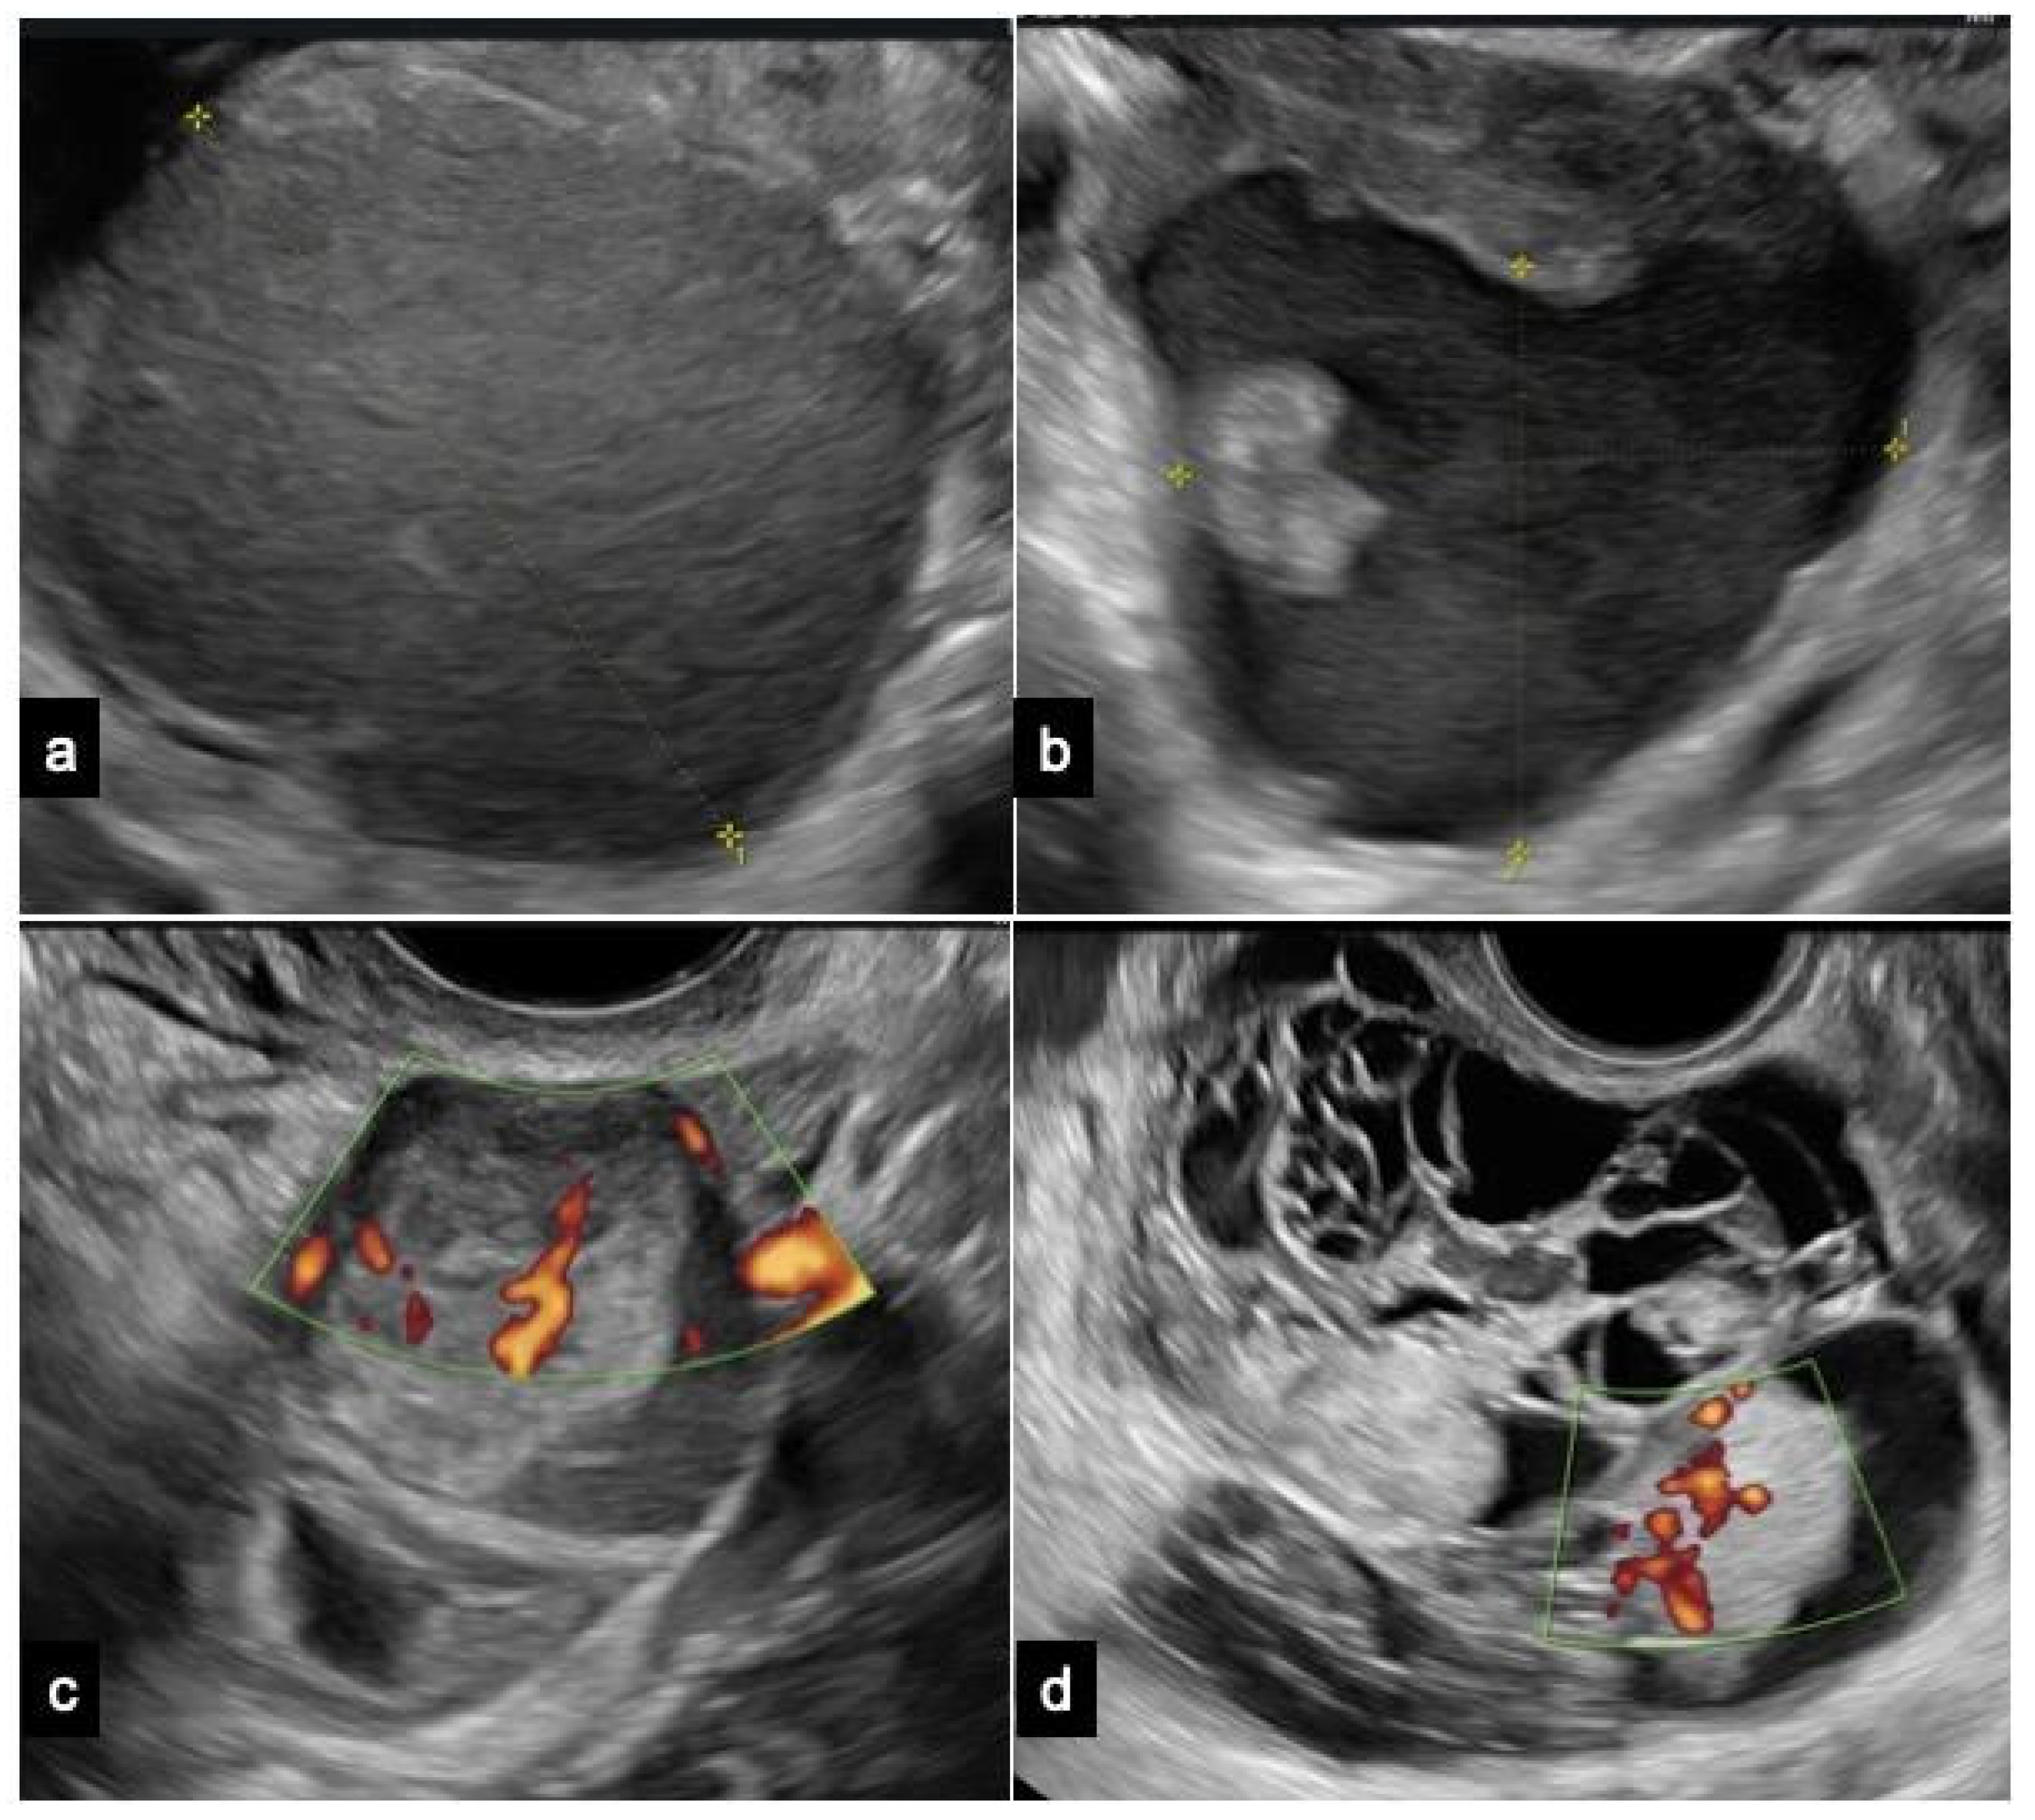

Figure 1.

Microscopic view of different grades of endometrioma atypia (50–100 μm): (A) typical endometrioma is lined by endometrioid epithelium with no endometrial stroma beneath it; (B) endometrioma with atypia showing nuclear pleomorphism, an inverted nucleus-to-cytoplasmatic ratio, and abundant eosinophilic cytoplasm with epithelial stratification and tufting; (C) endometrioma with foci of atypia (green arrow) and foci of clear cell carcinoma (blue arrow).